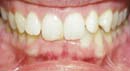

Hier können Sie einige Behandlungsergebnisse sehen

Mit dem Damon-System können wir Ihnen anbieten, was Sie wünschen - gerade und gesunde Zähne und ein wunderschönes Lachen auf schnellste und bequemste Art und Weise.

Diese zufriedenen Damon-Patienten erlebten alle eine gute Behandlungszeit - ohne das Ziehen von Zähnen, ohne einem Headgear oder rapid...

Tolle und schnelle Behandlungsergebnisse... |